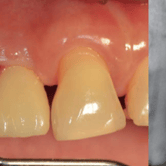

Frenillo labial hipertrófico

Un frenillo labial hipertrófico es una anomalía caracterizada por un frenillo labial superior grueso que puede causar problemas periodontales.

Los pacientes notan un pliegue de tejido muy grande entre su labio y su encía. Esto puede causar una separación entre los dientes delanteros y dificultar la higiene oral.

El tratamiento puede incluir una frenectomía para reducir el tamaño del frenillo